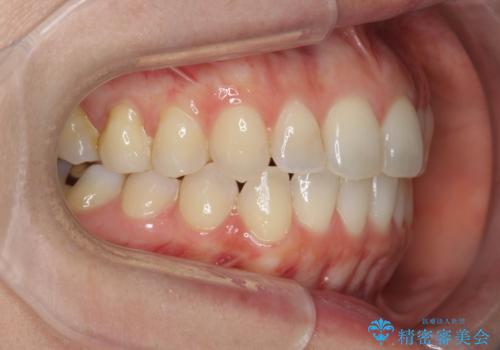

前歯のがたつきをしっかり治すマウスピース矯正

- 前歯のガタガタをきれいに並べたい、と希望され来院されました。

マウスピース矯正インビザラインのクリンチェックを用いて治療前にしっかりと歯並びのゴールのシミュレーションを行い、治療を開始します。

がたつきのないきれいな歯並びに仕上げることができ、満足いただくことができました。